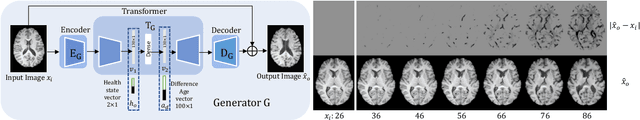

Abstract:Brain ageing is a continuous process that is affected by many factors including neurodegenerative diseases. Understanding this process is of great value for both neuroscience research and clinical applications. However, revealing underlying mechanisms is challenging due to the lack of longitudinal data. In this paper, we propose a deep learning-based method that learns to simulate subject-specific brain ageing trajectories without relying on longitudinal data. Our method synthesises aged images using a network conditioned on two clinical variables: age as a continuous variable, and health state, i.e. status of Alzheimer's Disease (AD) for this work, as an ordinal variable. We adopt an adversarial loss to learn the joint distribution of brain appearance and clinical variables and define reconstruction losses that help preserve subject identity. To demonstrate our model, we compare with several approaches using two widely used datasets: Cam-CAN and ADNI. We use ground-truth longitudinal data from ADNI to evaluate the quality of synthesised images. A pre-trained age predictor, which estimates the apparent age of a brain image, is used to assess age accuracy. In addition, we show that we can train the model on Cam-CAN data and evaluate on the longitudinal data from ADNI, indicating the generalisation power of our approach. Both qualitative and quantitative results show that our method can progressively simulate the ageing process by synthesising realistic brain images. The code will be made publicly available at: https://github.com/xiat0616/BrainAgeing.